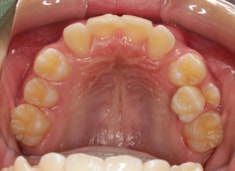

治療前

治療開始時

上下顎のギャップはありますが、顔面自体の幅径は良好な値を示していますので、スペース不足は拡大することによって解決できポテンシャルはあると考えられます。